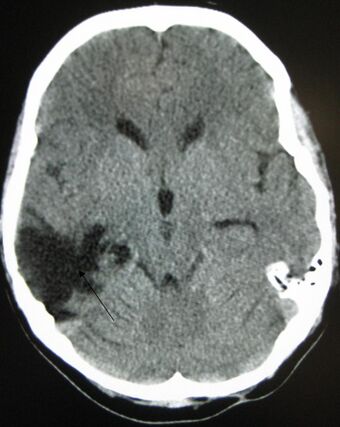

A CT of the head years after a traumatic brain injury showing an empty space where the damage occurred, marked by the arrow